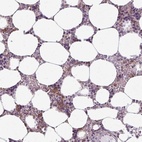

Immunohistochemical staining of human bone marrow shows positivity in hematopoietic cells.